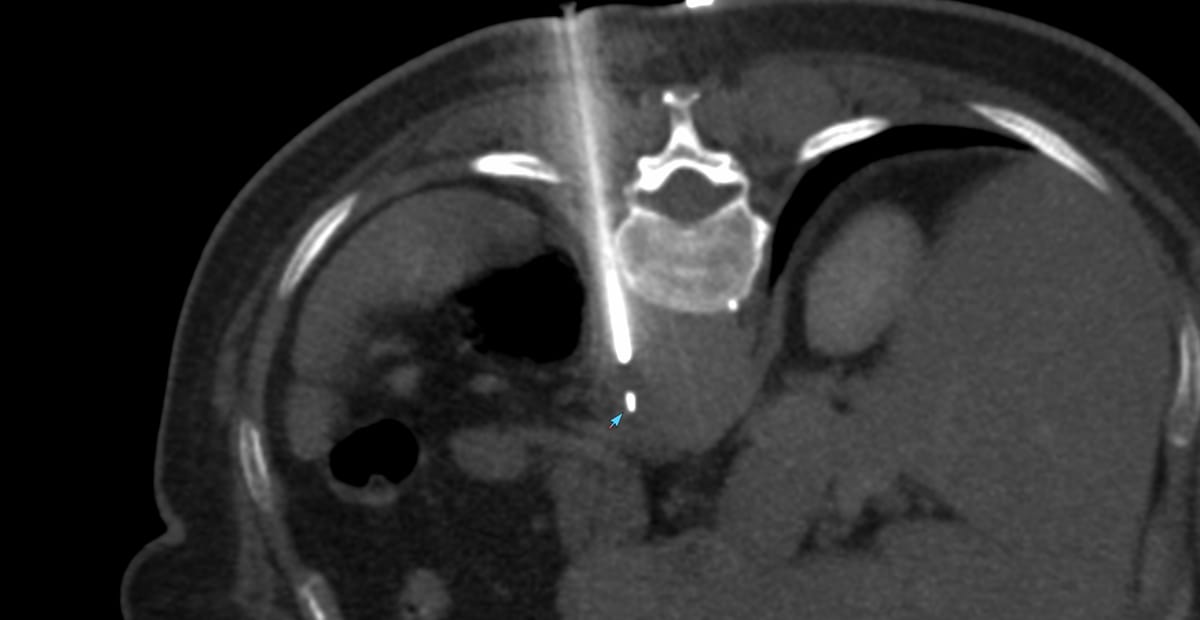

The patient came for a biopsy and I decided to use an anterior approach in the supine position.

Gun: 18G BARD, 20 mm throw, long

No of cores: 5 for HP

Position & Approach: Supine

Time Taken (marker to wash-out): 6 mins

Complication: 75 cc bleeding perisplenic stable after the 1st hour